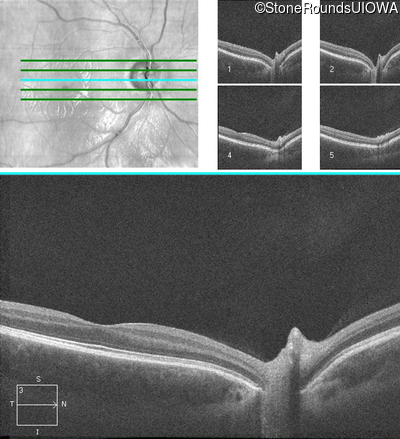

Age at visit: 17 years

OD OS

This 17 year old male had normal vision until about 6 months earlier when he began to lose central vision. The left eye may have been affected prior to the right eye.